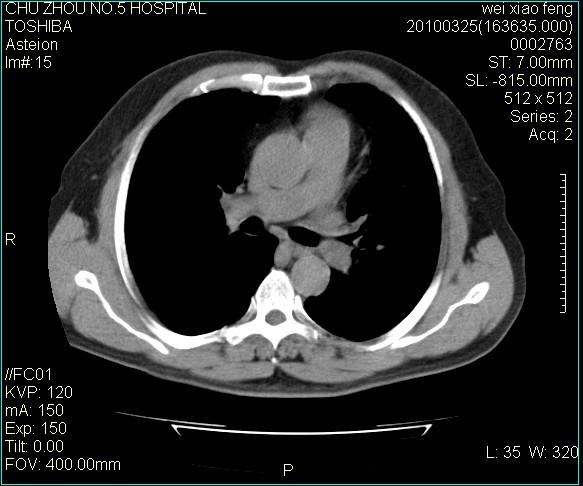

男,60岁,反复咳、痰、喘3月,加重3天。

心功能怎么样?感觉象肺淤血。

考虑间质性肺炎伴间质纤维化。

肺泡癌不除外